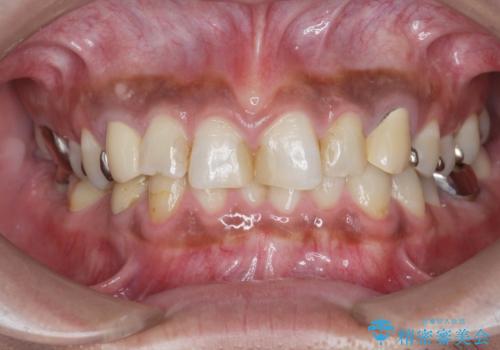

[メタルフリー] 虫歯・銀歯だらけの口腔内を全顎治療

![[メタルフリー] 虫歯・銀歯だらけの口腔内を全顎治療の症例 治療前](https://seimitsushinbi.jp/wp/wp-content/uploads/2025/03/e26a9887bc6905a2f0f51f5772b5ac9c-500x350.jpg?v=1741918285)